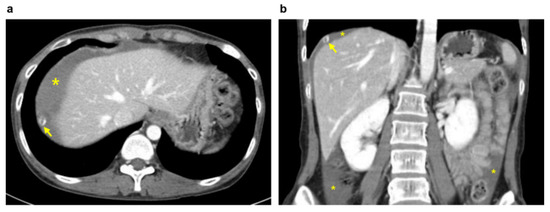

Figure 1. Abdominopelvic computed tomography images: A 2 cm target-like nodule with a thin, enhancing capsule (arrow); hemoperitoneum (*) in the axial (a) and coronal (b) planes.

A 34-year-old woman (gravida 3, para 3) with three spontaneous vaginal deliveries was transferred to the Ulsan University Hospital from a local clinic due to severe abdominal pain accompanied by right flank pain. The patient had been previously healthy and had no specific medical or surgical history. She had an irregular menstruation cycle, and her last menstruation occurred five weeks and six days previously. The initial vital signs at the emergency room were stable; systolic and diastolic blood pressure were 114 mmHg and 68 mmHg, respectively. The initial pulse rate was 71 beats per minute. Whole abdominal tenderness with muscle guarding was noted on physical examination. Blood tests showed a low hemoglobin level (10.7 g/dL). A urinary pregnancy test was positive, and the serum β-HCG level was 7377.0 mIU/mL. Gynecological sonography found no evidence of an intrauterine pregnancy, except for normal bilateral adnexa with free fluid collection, suggestive of hemoperitoneum. After eight hours, the follow up blood test showed a lower hemoglobin level (8.6 g/dL). Two packs of packed red blood cells were transfused. We suspected a ruptured ectopic pregnancy through elevated serum β-HCG, but the ectopic mass could not be identified on pelvic ultrasound. Thus, we planned abdominopelvic computed tomography (APCT) to determine the cause of the right frank pain. Approximately 2 cm hypervascular mass in the subphrenic region, with a moderate amount of hemoperitoneum, was revealed (Figure 1), which was thought to be the cause of the bleeding. Because of suspicions of a diaphragmatic ectopic pregnancy or other ruptured unknown hepatic mass, she was admitted for emergency surgery. Diagnostic laparoscopic surgery was performed in collaboration with a hepatobiliary surgeon and an obstetrician-gynecologist. On laparoscopy, about 400 mL of blood and clots were aspirated from the pelvic cavity, but both adnexa appeared normal. Approximately 20 × 10 cm tissue, suspected to be the placenta with a hematoma, had covered the diaphragm. After the removal of the placenta-like tissues, we found a 2 cm hypervascular mass attached to the diaphragm (Figure 2). The mass was completely resected from the diaphragm and sent for histological examination. After the surgical mass removal, the patient was discharged without any postoperative complications, and the serum β-HCG level normalized within a month. The final pathologic diagnosis indicated that the mass was a product of conception, consistent with an ectopic pregnancy (Figure 3).